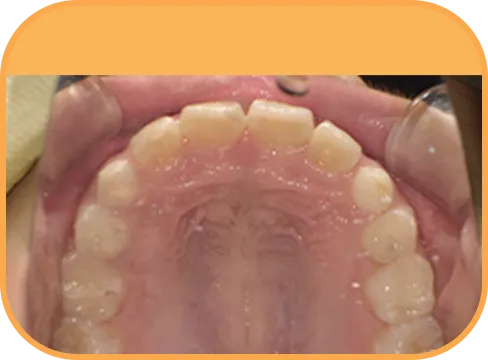

• After

• 上 顎

治療後上顎からの歯の様子

主 訴

前歯が開いている

治療内容

インビザライン・ファースト

治療期間

6か月

治療費(税別)

450,000円+診断料30,000円

リスク・副作用

• 親知らずの影響や加齢などによって、凸凹が生じる可能性があります。

• 治療の初期段階では痛みや不快感が生じやすくなりますが、1週間前後で慣れます。

• 顎の成長発育によって、噛み合わせや歯並びが変化する可能性があります。

• 状況により当初予定した治療計画を変更する可能性があります。